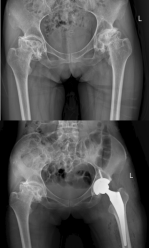

起初,髋关节的隐痛如同身体发出的微弱警报,却在张大姐对抗病痛的日常中被忽略了。髋关节的疼痛从偶尔的“警报”逐渐演变为持续不断的“呻吟”。张大姐形容,后期每一次挪步,都感觉髋部像是“生锈的旧门轴”,在转动时发出艰涩的摩擦与刺耳的咯吱声,不仅疼痛钻心,更伴随着明显的不稳定感。医院的影像检查报告揭示了残酷的真相:她双侧的股骨头——那个本该表面光滑、在髋臼内灵活转动的球状结构——已经发生了灾难性的完全塌陷,外形扭曲变扁,从“圆球”变成了“被压扁的圆锥”,关节间隙几乎消失。这直观地解释了为何她的活动能力被严重禁锢。

手术台上,科技力量为精准医疗插上了翅膀。张还添教授团队为张大姐实施了“机器人辅助下全髋关节置换术”。这套先进的手术机器人系统,犹如为外科医生装配了“超级视觉”和“稳定机械手”。术前,基于患者个性化的三维CT数据,机器人系统已规划出匹配度最高的假体型号、安装位置和角度,精度达到亚毫米级。当手术视野打开,医生们亲眼所见的情形比术前影像更为震撼:那颗塌陷的股骨头形态怪异,严重变形,确实如同一个被紧紧束缚、失去原本饱满形态的“旧式粽子”。在机器人辅助下,病变的股骨头被精准移除,一个适配性佳的人工关节假体被稳稳地植入预定位置,重建了髋关节正常的力学结构与旋转中心。